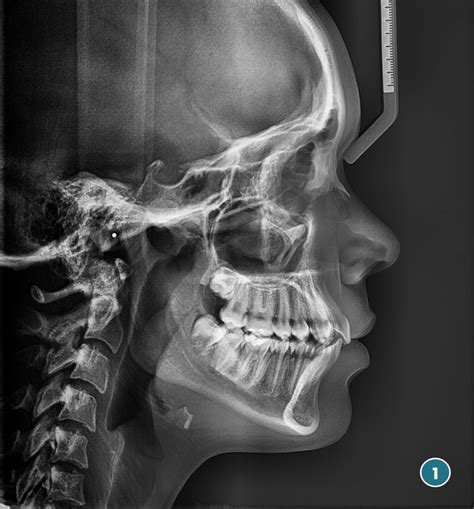

Una telerradiografía lateral de cráneo es un tipo específico de radiografía que muestra una imagen precisa y detallada de la cabeza vista desde un lado (lateralmente). Se le llama telerradiografía porque la imagen se toma desde una distancia fija, generalmente alrededor de 1,5 metros, con el fin de reducir al mínimo cualquier posible distorsión o ampliación.

Este espacio adicional (el paciente se coloca a 2 metros de la placa) evita que la imagen se vea distorsionada por las estructuras óseas del cráneo. Las telerradiografías de cráneo pueden ser frontales (realizadas con el paciente “de cara”) o laterales (de perfil). Estas radiografías son una parte fundamental de los estudios de ortodoncia, ya que permiten medir los ángulos y proporciones de los huesos de la cara del paciente y de este modo conocer la relación entre sus estructuras faciales.

El estudio cefalométrico de la radiografía lateral del cráneo nos permitía diagnosticar los problemas de la maloclusión tanto en el plano sagital (clase I, clase II, clase III) como el plano vertical (Mordida abierta, sobremordida) quedando un plano tan importante, como es el plano transversal, sin ser analizado de forma cefalométrica.